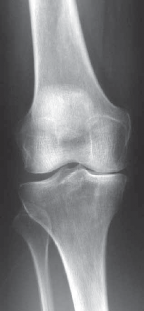

Meticulous preoperative imaging is the cornerstone of successful UKA planning. Plain radiographs must include a weight-bearing anteroposterior (AP), a true lateral, a Rosenberg (45-degree flexion weight-bearing posteroanterior) view, and a Merchant or sunrise patellar view. These images are critical in determining whether the patient is an appropriate candidate. If only medial compartment arthritis—evidenced by joint space narrowing, subchondral sclerosis, cystic changes, and osteophyte formation—is appreciated on the standard AP view, a valgus stress view is absolutely mandatory.

The valgus stress radiograph is arguably the most important image in the UKA workup. It serves two critical functions: first, it demonstrates the normal thickness of the cartilage in the lateral compartment by opening the lateral joint space; second, it proves whether the medial varus deformity is passively correctable. On a proper valgus stress view, the lateral compartment should gap appropriately, and the lateral cartilage space should not measure less than 5 mm (representing the sum of the thickness of normal femoral and tibial cartilage). Conversely, the medial compartment should gap at least 5 mm, representing the sum of the articular cartilage lost.

Incomplete loss of the medial joint space on a standard AP must be investigated further with a varus stress view to confirm complete joint space loss. If the joint space loss is not full-thickness (i.e., not bone-on-bone), UKA should generally be avoided, as the outcomes for partial cartilage loss are significantly inferior, and other sources of pain (e.g., meniscal pathology, radiculopathy) must be sought.

The lateral radiograph is a highly reliable, albeit indirect, indicator of the functional integrity of the ACL. Because anteromedial OA features preserved posterior cartilage due to normal kinematic roll-back, the lateral film can reveal the extent of posterior wear. For accurate assessment, the femoral condyles and the medial and lateral tibial plateaus should appear perfectly superimposed.

Clinical & Radiographic Imaging Archive